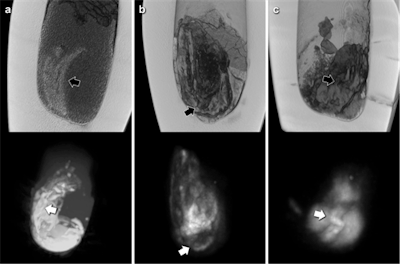

The low amount of water present in the desiccated jar contents limited image quality of MRI scans. Nevertheless, areas of pronounced signal intensity coincided well with hyperdense structures previously identified on CT scans, according to the researchers. CT-based volumetric calculations revealed holding capacities of the jars of 626 cm3 to 1,319 cm3 and content volumes of 206 cm3 to 1,035 cm3.

The CT findings also raise the question of whether the examined canopic jars do hold entire mummified human organs. The structures identified in canopic jar 607 would be far more compatible with a small organ fragment (potentially intestine) rather than an entire mummified organ, they wrote. The MR images corroborate this, and the observed pronounced variations in signal intensity coincide very well with the organ fragment notion.